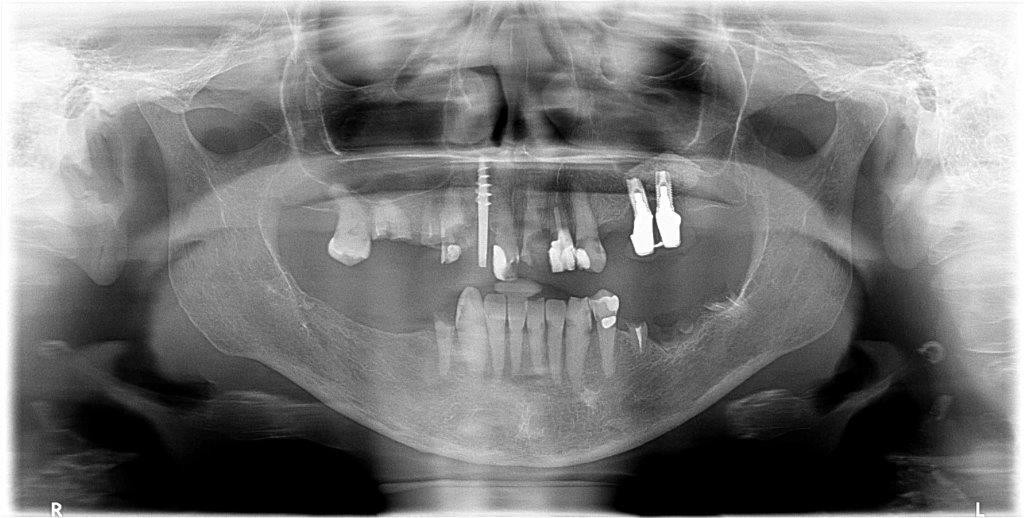

Per mostrarti che questo non è un caso limite di uno studio singolo ti mostro la panoramica di una visita delle 16 dello stesso giorno.

Questa signora, affetta da sarcoidosi per cui da anni assume glucocorticoidi (Deflan) e da epatite C per cui sta eseguendo una terapia con sofosbuvir e ribavirina si ripresenta in lacrime per la sua condizione. Il dentista continua a fargli lavori nel settore frontale che non tengono. Il 21 si è distrutto per metà e lei non esce più da giorni per questo (i pazienti a volte sono strani, lo sappiamo…in questa bocca il 21 mezzo rotto era l’ultimo dei problemi…). La signora mi dice che il dentista ha provato a trattare il 13 ma le ha detto che “non riusciva a trovare il canale perché c’è dell’osso, non ho capito bene…” E ha appuntamento per vedere che si può fare sul 13 tra una settimana, perché è andata da una catena odontoiatrica che ad agosto sarà aperta (almeno questo! ?). E nel frattempo mi chiede se il 22 va bene perché gliel’ha fatto l’ultima volta!

Evito i commenti sul tentativo di recuperare i denti volta per volta in questo caso.

Se anche la paziente non avesse i soldi per togliere tutto e affrontare una riabilitazione fissa su impianti non si può di sicuro invocare l’etica e la compassione nel tamponare una situazione del genere! Piuttosto di spillare qualche centinaio di euro ogni volta su terapie che poi non si possono garantire al paziente togli tutto e fai una dentiera! Stop! Non ci sono altri piani di cura qui!

La bonifica completa nell’arcata superiore in questo caso dovrebbe essere il primo passo comune di un piano di cura per tutti i dentisti, a meno che non si vogliano salvare per qualche astrusa teoria di “voler conservare” il 17, l’11 e gli impianti in perimplantite per tentare di ancorare una protesi parziale, ma non ha alcun senso, a parer mio.